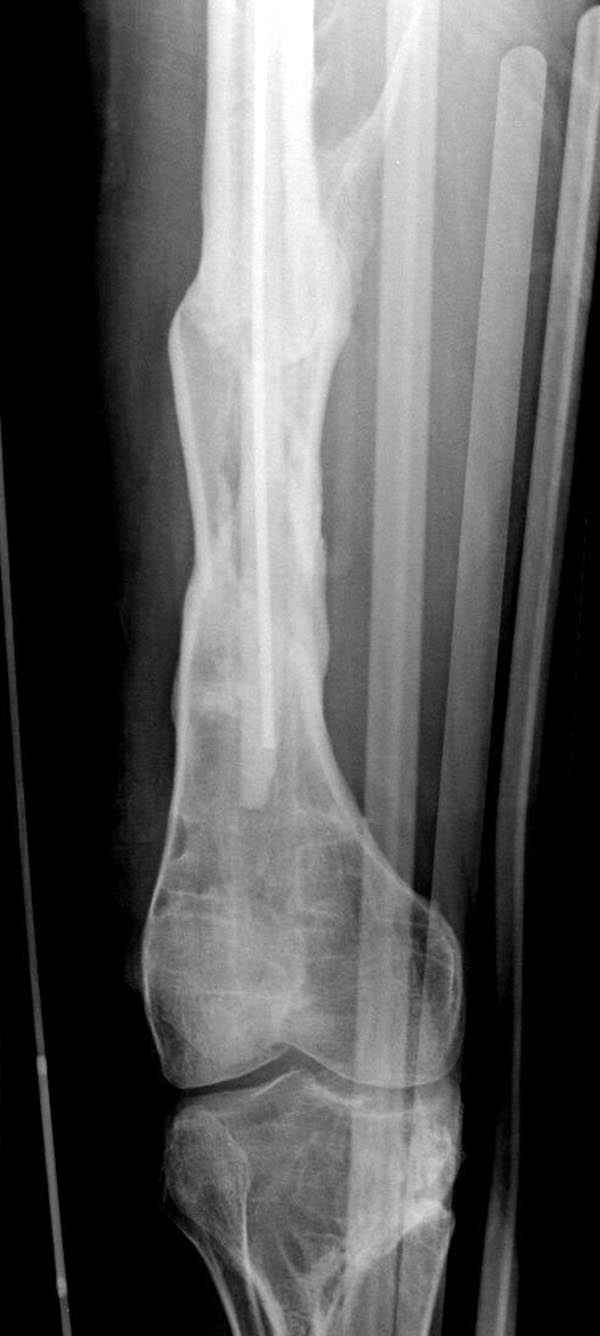

Мы не дождались “Happy End”, у больного IQ в пределах 70%, через 6 месяцев вернулся после небольшой травмы, споткнувшись получил перелом

того же бедра (рис №7).

На следующий день произвели интрамедуллярный остеосинтез: этапы во время операции (рис №8, №9)

и последующих снимках (рис №10, 11, 12, 13) перелом сростается и передвигается с полной нагрузкой.

При обзоре причин перелома, на снимке №2 обнаружили, что один из стержней аппарата наружной фиксации проходил только через передний кортекальный слой, что создало стрессовую зону на бедре и в результате перелом из-за незначительной травмы.